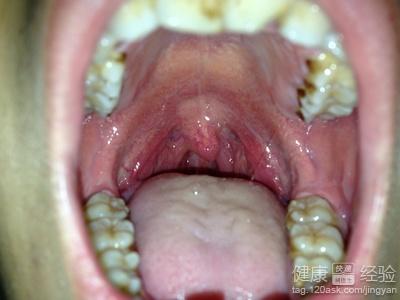

嗓子發炎了通常也成為扁桃體發炎,扁桃體發炎其實是一個很常見的疾病哦。有的孩子不僅僅有扁桃體發炎而一起你喉嚨隱隱作痛的症狀。甚至部分孩子還比較容易因此就產生一些感冒的症狀哦。這疾病的主要病因是由於抗病能力的低下,而且和細菌感染造成的。扁桃體發炎這個疾病其實需要去醫生去咨詢相關的治療方法。扁桃體發炎怎麼辦?茶療與食療齊幫助?下面一起看看哦。

1扁桃體發炎的時候需要藥物的治療。而且需要多喝水哦。這個時候茶療與食療齊幫助。扁桃體炎的病人可以吃一些新鮮餓烏龍茶哦。茶葉裡面的茶多酚往往可以起到抗氧化的效果。那麼對身體比較好。

3扁桃體發炎的病人不僅僅可以吃一些茶葉,而且需要進一步去口服消炎藥去治療。為了提高抗病能力,而且還需要進一步去補充維生素C外的症狀可以用清熱瀉火的中藥治療。比較好的了。